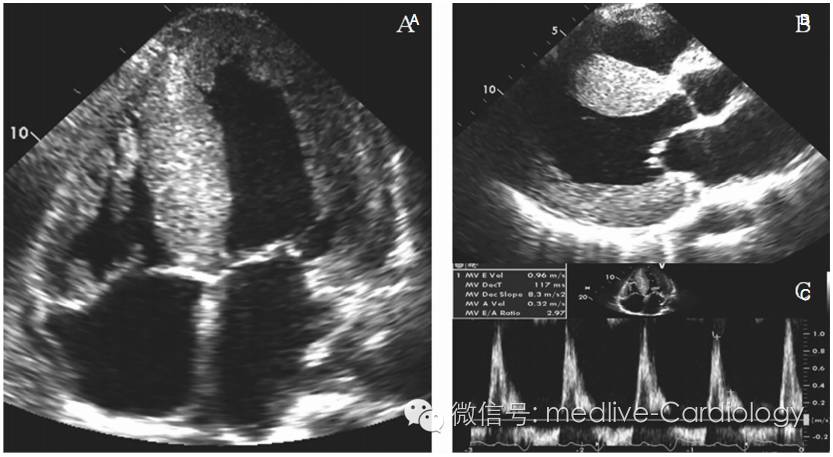

LD,男性,67岁,既往脑卒中病史,考虑脑缺血或自发性血栓形成引起。现神经系统症状已恢复,但仍有活动后乏力,再次就诊时出现新发的心房颤动。超声心动图及多普勒超声提示:LVEF正常,左室舒张功能下降,左室中度肥厚,室间隔非对称性增厚,双房扩大,轻度肺动脉高压。诊断基本排除肥厚性心肌病,给予β受体阻滞剂和利尿剂治疗。除此之外,患者仍有严重的活动后乏力症状,仅能在室内行走,并且出现双下肢水肿。尝试应用抗心律失常药物氟卡尼及索他洛尔转复AF,但不能维持窦性心律。复查超声心动图及多普勒超声:左室收缩功能保留,但病情加重,双心室扩大、室壁变薄,严重的右室功能不全,严重的左室舒张功能下降伴二尖瓣反流,肺动脉压较前明显升高达105mmHg(图3)。体格检查:血压118/68mmHg,心率67次/分,颈静脉压20cmH20(约1960Pa),肝颈静脉回流征阳性,可闻及第4心音,二尖瓣收缩期杂音,右肺呼吸音减低,右侧胸腔积液,双下肢对称性水肿 。

图3超声心动图:心肌淀粉样变性。(A)心尖四腔切面;(B)胸骨旁长轴切面;(C)限制性多普勒表现。

分析患者存在双室增厚、心肌受限、胸腔积液,推测患者为淀粉样心肌病。血液、尿液中轻链蛋白水平升高,骨髓活检提示35%为浆细胞。取脂肪组织切片进行刚果红染色,也证实患者为免疫性轻链蛋白型淀粉样心肌病。初始给予硼替佐米和地塞米松治疗,后加用来那度胺,治疗期间如双下肢水肿加重则加量利尿剂。